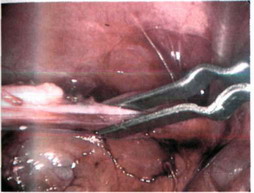

Р"С_ 1б"9_ Пересечение gubernaculum testis.